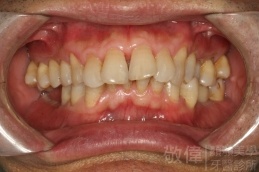

| 10 | 前牙美容 | 快速矯正之牙冠增長術+美容晶瓷貼片 |